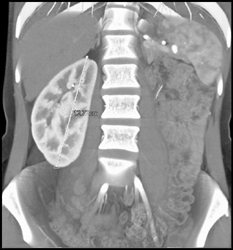

Right Hydronephrosis and Pyelonephritis